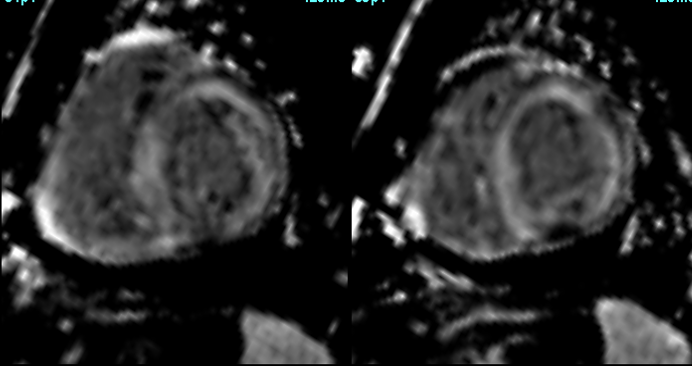

COD 077 - Decoding Septum Predominant Hypertrophic Cardiomyopathy

Understanding standard septum predominant HCM